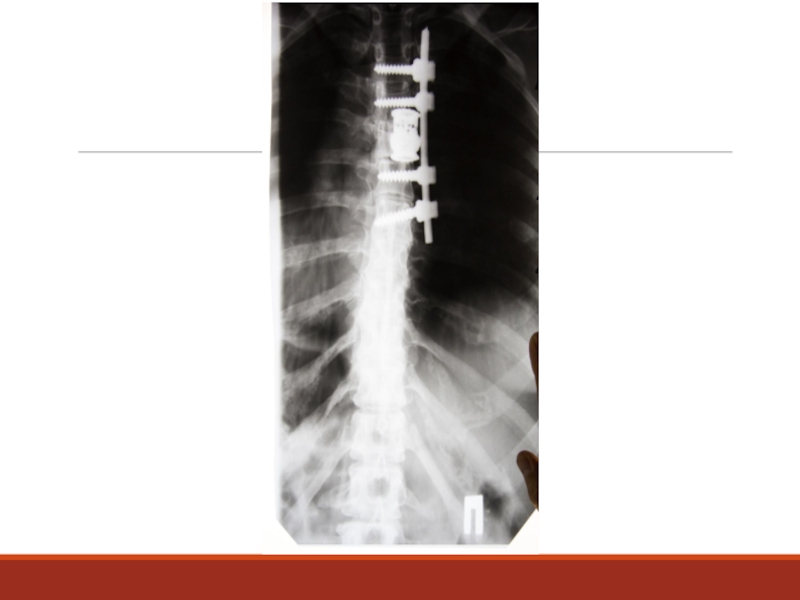

Слайд 38Нарушение осанки, сколиоз

Слайд 51Абсолютные показания к операции при пояснично-крестцовой радикулопатии

1. Сдавление корешков конского хвоста

с парезом стоп

2. Анестезия аногенитальной области

3. Нарушение функции тазовых органов

4. Нарастание пареза в миотоме пораженного корешка

Слайд 52Относительные показания при шейной и поясничной радикулопатии

Выраженный корешковый (невропатический) болевой

синдром не поддающийся адекватному лечению в течение 6 нед., а также нарастание неврологических нарушений.